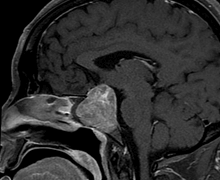

Case 1: 35/ M

- Pre-operative Coronal and Sagittal contrast enhanced T1W images show a well circumscribed homogenously enhancing sellar mass with suprasellar extension (Figure 1).

- Intra-operative coronal and sagittal T1W (Figure 2) contrast enhanced sequences show no residual enhancing tumour in the post operative bed (Figure 3).

Figure 1

Figure 2

Figure 3